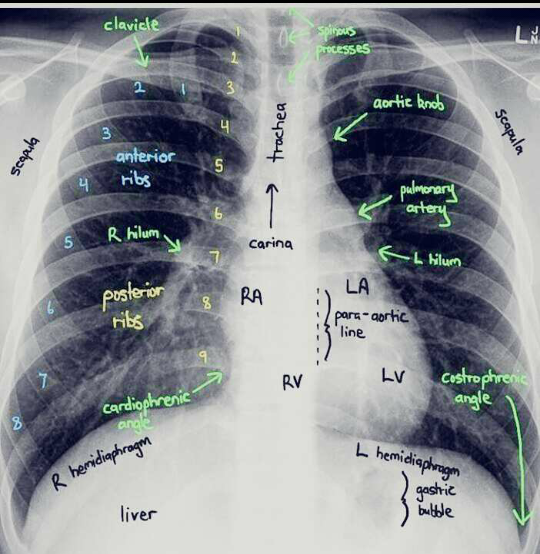

X-ray of thorax

Where do you put the needle if someone had a tension phenomothorax?

The most common and effective way of dealing with a punctured lung is by the insertion of a chest tube or hollow needle. For this procedure, we inserts a hollow needle or chest tube into the pleural space to let the air out.